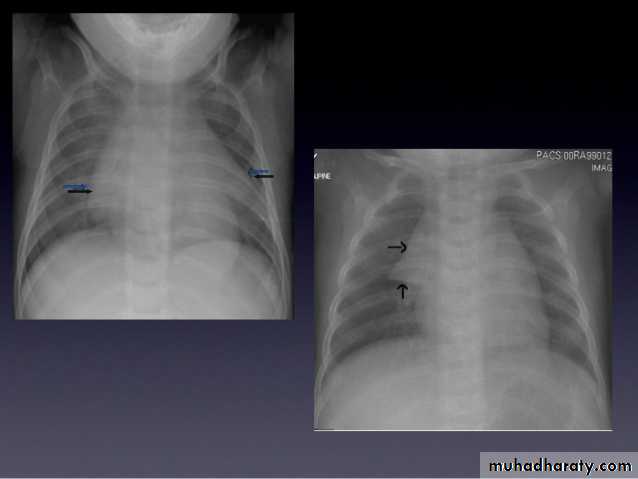

Lymph adenopathy

Bilateral hilar LAP

28.chest XR ( bilateral hilar lymph adenopathy )

29.chest XR ( bilateral hilar lymph adenopathy )